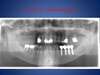

Prothèse fixe transvissée